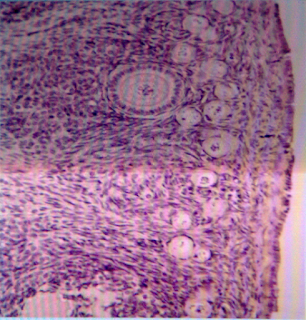

OVARIO 10X